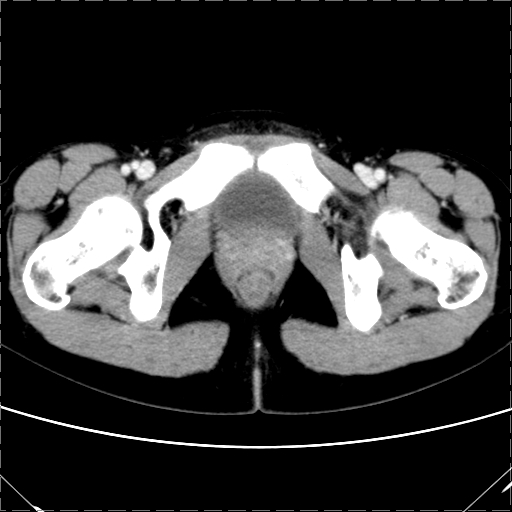

女 29岁 突然腹部疼痛1天 b超示子宫左后方肿块。月经正常。

影像表现复杂,膀胱上见一囊性包块,比膀胱密度高,其内有不均匀稍高密度,似与道格拉斯窝肿物无分界,病灶没有张力,因其腹平坦,推定其具有流动性,但又似见包膜,而b超没有报告这一现象。确实没见过。考虑卵巢囊肿蒂扭转并囊内出血可能。

病变主要位于道格拉斯窝,而且大体形态比较扁平且贴合子宫直肠,无明显张力及对周围脏器压迫,所以考虑为液体,而中间可见囊样病变伴环形强化,期内还可见分隔影,结合突发急性腹痛故多考虑囊腺瘤伴破裂出血。

腹腔镜术后 卵巢黄体囊肿破裂出血